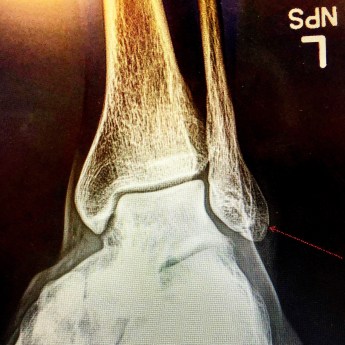

Technically I had a closed avulsion fracture of the lateral malleolus of my left fibula, an injury that’s going to keep me on crutches for about two weeks and in an air cast until at least the second week of July. Basically, a small chunk of my ankle bone was pulled away by a tendon when my left foot landed sideways and it will take 6-7 weeks to heal. After consulting with Dr. Adam Miller at Beacon Orthopaedics and Sports Medicine, I was relieved to hear that surgery shouldn’t be necessary. That said, being largely immobile for the entirety June isn’t much of a consolation prize.